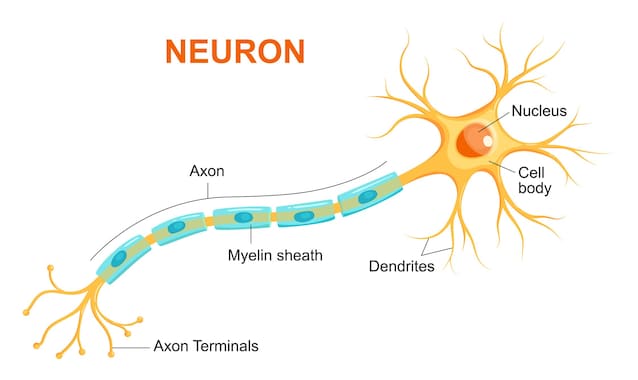

La Sclerosi Multipla (SM), come spiega l'AISM (Associazione Italiana Sclerosi Multipla), è una malattia neurodegenerativa cronica complessa che colpisce il Sistema Nervoso Centrale (cervello, midollo spinale e nervi ottici). Si tratta di una patologia autoimmune in cui il sistema immunitario attacca per errore la mielina, la sostanza composta da lipidi e proteine che riveste e isola le fibre nervose dei neuroni: il suo ruolo è analogo alla guaina di plastica di un filo elettrico. Questo attacco causa la perdita di questa protezione – la demielinizzazione – e la formazione di cicatrici chiamate sclerosi. I segnali nervosi che partono dal cervello vengono in questo modo rallentati o bloccati, causando i sintomi della malattia che possono variare molto da paziente a paziente.

Il team guidato dal professor Roland Martin si è concentrato sui Linfociti B, le cellule che producono gli anticorpi. Lo studio ha rivelato che il virus EBV infetta queste cellule e le "riprogramma", inducendole a esporre sulla loro superficie frammenti della Proteina Basica della Mielina (MBP) legati alle molecole HLA-DR15. Questa esposizione inganna i Linfociti T che, riconoscendo questi complessi molecolari come una minaccia, si attivano erroneamente contro il tessuto nervoso. Il risultato è un attacco diretto alla guaina mielinica nel cervello e nel midollo spinale. Il danno progressivo a questo strato protettivo compromette la capacità dei neuroni di trasmettere i segnali elettrici, scatenando i sintomi della malattia.